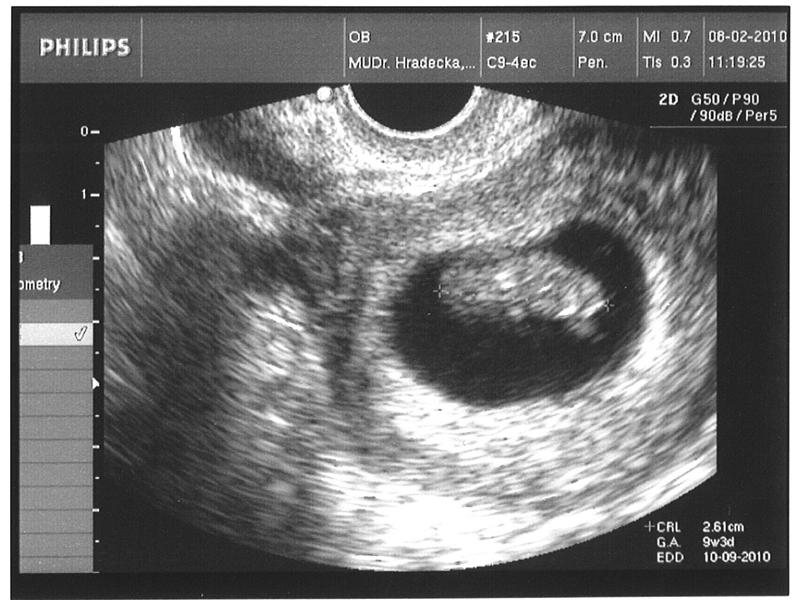

Vývoj otazníčka